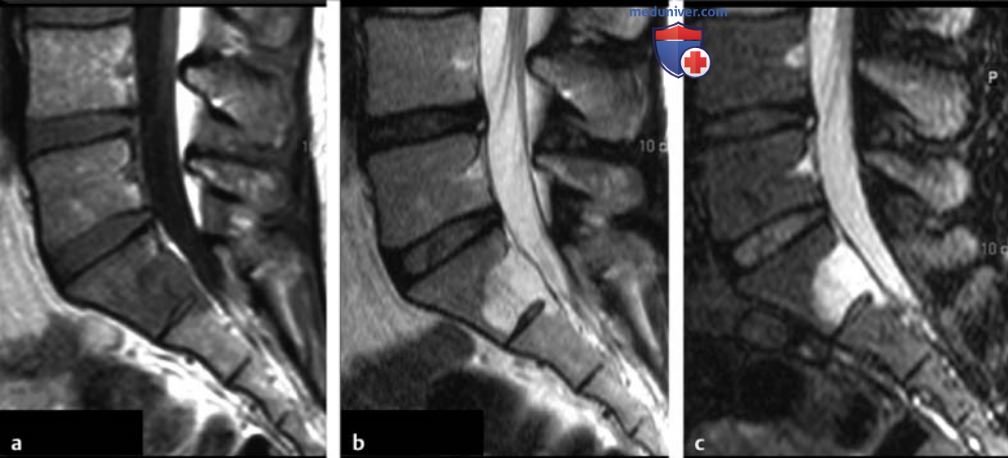

Рисунок 1. а-c Кортикальная остеоид-остеома большеберцовой кости.

а Т1в-SE-изображение в сагиттальной плоскости.

b Т2в-SE-изображение в аксиальной плоскости.

c Т1в-SE-изображение с контрастированием. Нидус диаметром примерно 4 мм (стрелки) виден в заметно утолщенном кортикальном слое диафиза большеберцовой кости. На аксиальном срезе отмечается реактивный отек костного мозга, а также периостальный и параостальный отек мягких тканей, окружающий большеберцовую кость (головки стрелок).